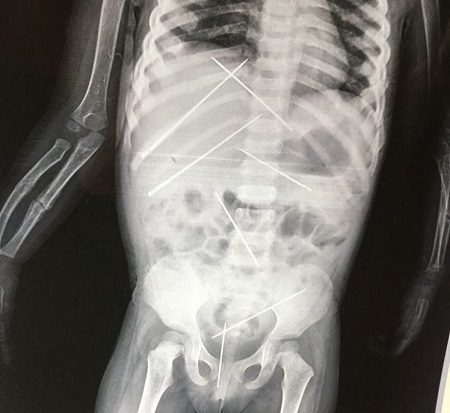

An X-ray shows the needles that were shoved into the young girl’s body (Picture: SWNS)

These are the horrifying X-ray pictures showing seven two-inch long pins stuck inside a three-year-old girl by a man accused of torturing her using ‘black magic’.

Doctors discovered there were several needles inserted in her abdomen and she had a broken arm.

Seven pins had to be surgically removed from her body (Picture: SWNS)